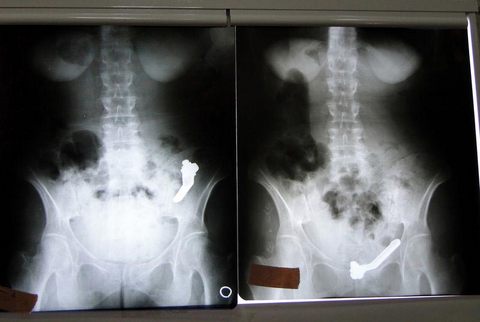

Van'da mide ağrısı şikayetiyle hastaneye kaldırılan kadının bağırsağından, 10 santimetre uzunluğunda vana kolu çıktı.

Alınan bilgiye göre, evindeki 10 santimetre uzunluğundaki metal vana kolunu yutan F.G, bir gün sonra şiddetli mide ağrısı şikayetiyle İpek Yolu Devlet Hastanesine kaldırıldı.

Yapılan tetkiklerde F.G'nin midesinde 10 santimetre uzunluğunda metal bir cismin bulunduğu görüldü. Doktorlar, vana kolu olduğu belirlenen cismin doğal yollarla vücuttan atılmasını bekledi.

Ancak midenin ardından kalın bağırsağa yerleşen cismin doğal yollardan vücuttan atılmayacağını tespit eden doktorlar, hastaya operasyon yapılmasına karar verdi. Yaklaşık 40 dakika süren operasyonda vana kolu bağırsaktan çıkarıldı.